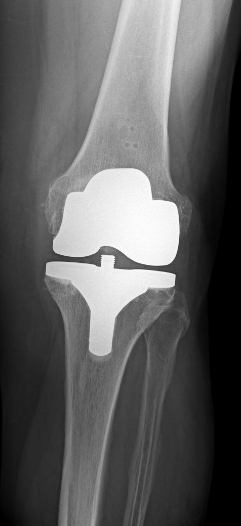

Kniegelenksersatz mit Computer-assitierte Navigation